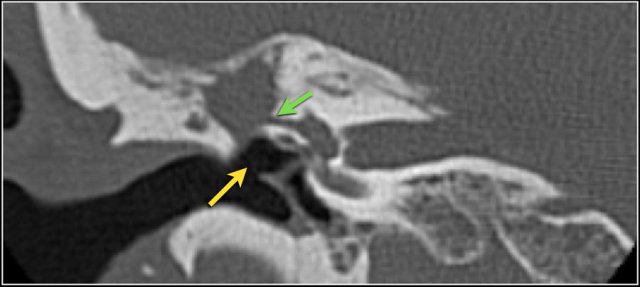

Facial nerve

The labyrinthine segment of the facial nerve coming from the internal auditory canal angles sharply forward, nearly at right angles to the long axis of the petrous bone, to reach the geniculate ganglion.

At the ganglion the facial nerve makes a U-turn (first genu of the facial nerve) to run posteriorly as the tympanic segment along the medial wall of the epitympanum.